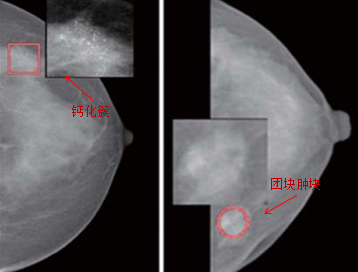

3、检测

计算机辅助检测是利用先进的计算机软硬件来分析和处理医学图像,以发现并检出病变,从而辅助医生临床诊断,提高工作效率。

方法:特征分析法、双能量减影法和时间减影法。

应用:乳腺、胸部。

检测(作用)

乳腺:可提供乳腺癌诊断的敏感度,降低致密型乳腺内病变、直径小的钙化灶、导管内癌及浸润性导管癌的漏诊率。

胸部:胸片的心脏和肺野的自动分析,肺结节、气胸的检测,肿块和钙化的分类、鉴别。